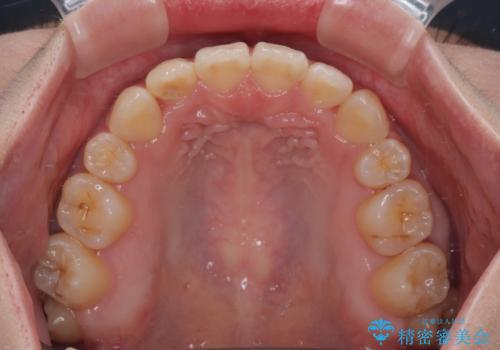

デコボコだらけの歯列をきれいに ワイヤー装置での抜歯矯正治療

- 上下前歯のデコボコを気にして来院された患者様です。

口元の突出感はあまりなかったものの、デコボコを非抜歯で改善すると出っ歯になる可能性があるため、上下左右の第一小臼歯4本を抜歯し、ワイヤー装置にて矯正治療を行うこととしました。